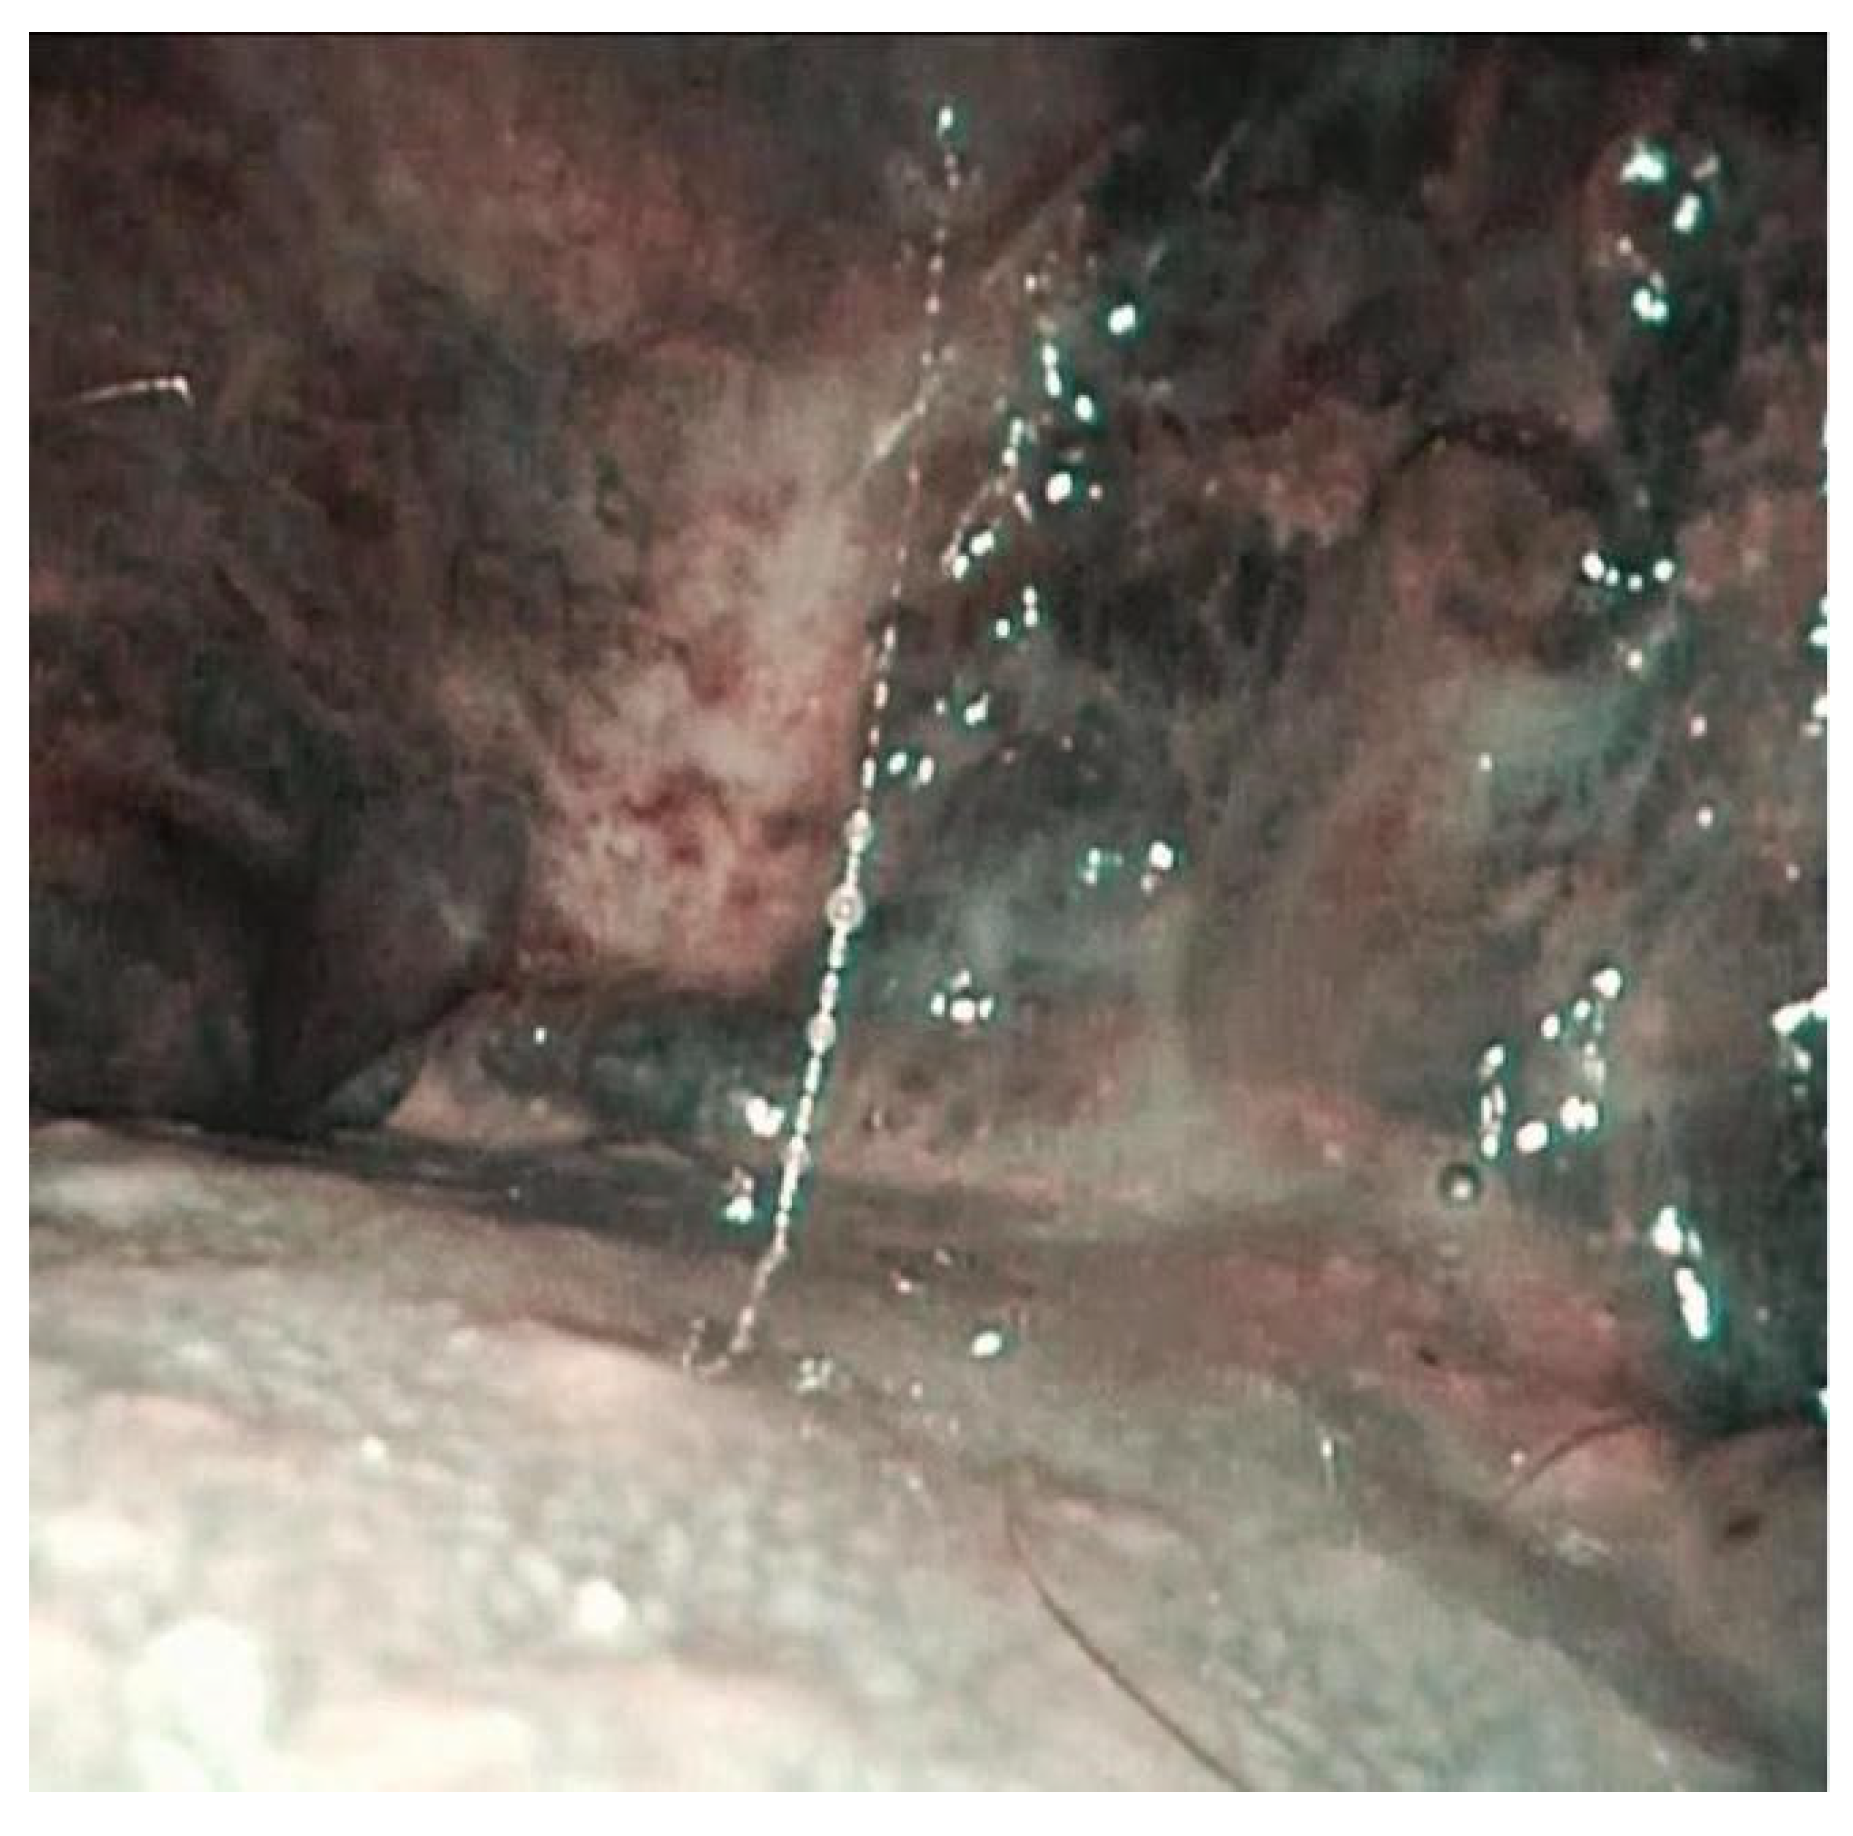

| 7 | Bilateral buccal mucosa and tongue. | Ulcerative lesion on the left buccal mucosa with augmented peripheral vascularization. Erythematous appearance of the tongue with inflammation and edema of the lingual papillae. | Evidence of ulcerative lesion of the left buccal mucosa with erythroplasia-like changes and abnormal vascularization on its margins. | Evidence of dark spots on the border of the ulcerative lesion of the left buccal mucosa. | Delayed because of recurrence of intestinal adenocarcinoma. |